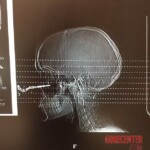

CANADA – JANUARY, 2023 24-year-old Renee Lariviere left her car keys at home. So she called for her boyfriend to throw them out the window. But she didn’t catch the key and it was stuck right in her face. It missed her eye by a few millimeters. The doctors called to the scene were amazed and even took pictures of her, as this is an extremely rare case.

- Renee Lariviere 3